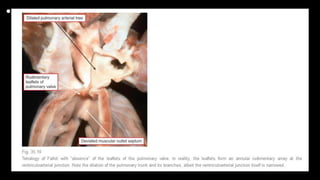

n this specimen, again photographed as for

Figure 1, the defect extends to the level of the

pulmonary valve due to failure of

muscularisation of the outlet septum during

development of the heart. This type of defect

is doubly committed and juxtaarterial, but is

also perimembranous.

This specimen has tetralogy of Fallot with

pulmonary atresia. The pulmonary supply is

through multiple systemic-to-pulmonary

collateral arteries. The star shows the

connection between one of the collateral

arteries and the intrapericardial pulmonary

arteries. All the other arteries join with the

intrapericardial pulmonary arterial supply, or

else supply segments of the lung directly. The

task of the clinician is to display the supply of

the various collateral arteries and their

communications with the intrapericardial

pulmonary arteries.